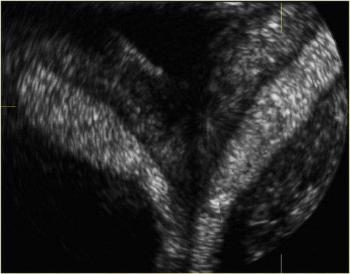

Normal 35 week pregnancy